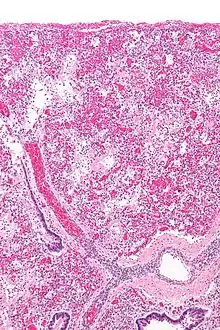

Leukocyte-mediated pulmonary inflammation is a key pathophysiological mechanism involved in ARDS.[2] This is presumed to cause Diffuse Alveolar Damage (DAD) [Fig 2]. On histologic examination, DAD is present in 40-60% of patients clinically diagnosed as having ARDS.[3]